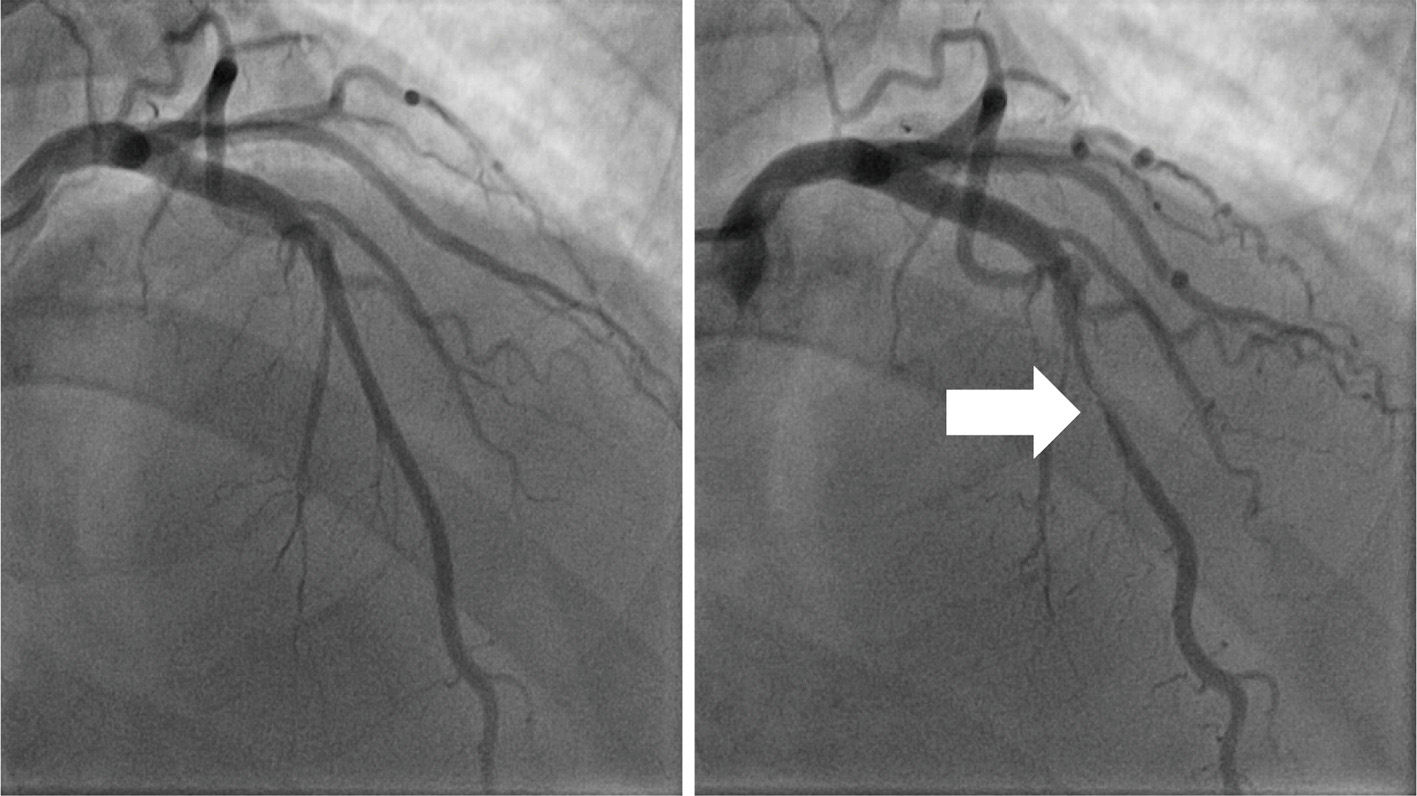

Myocardial bridging mimicking Wellens’ syndrome Pederçole Journal Journal Of Xiangya Medicine Find the latest published papers in journal of xiangya medicine + top authors, related hot topics, the most cited papers, and related. Journal of xiangya medicine is a journal covering the technologies/fields/categories related to. Gab1, a therapeutic target for allergic. Published by ame publishing company. The journal of xiangya medicine publishes invited articles solicited from recognized experts in their fields. Journal Of Xiangya Medicine.